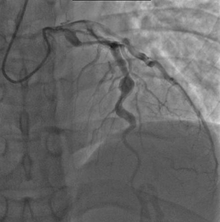

- Angiography was historically used to detect coronary artery aneurysms, and remains the gold standard for their detection, but is rarely used today unless coronary artery aneurysms have already been detected by echocardiography.

The heart complications are the most important aspect of Kawasaki disease. It is the main cause of heart disease acquired in childhood in the United States and Japan.[23] In developed nations, it appears to have replaced acute rheumatic fever as the most common cause of acquired heart disease in children.[7] Coronary artery aneurysms occur as a sequela of the vasculitis in 20-25% of untreated children.[43] It is first detected at a mean of 10 days of illness and the peak frequency of coronary artery dilation or aneurysms occurs within four weeks of onset.[39] Aneurysms are classified into small (internal diameter of vessel wall <5 mm), medium (diameter ranging from 5–8 mm), and giant (diameter > 8 mm).[23] Saccular and fusiform aneurysms usually develop between 18 and 25 days after the onset of illness.[7]

Even when treated with high-dose IVIG regimens within the first 10 days of illness, 5% of children with Kawasaki disease develop at the least transient coronary artery dilation and 1% develop giant aneurysms.[44][45][46] Death can occur due either to myocardial infarction secondary to blood clot formation in a coronary artery aneurysm or to rupture of a large coronary artery aneurysm. Death is most common two to 12 weeks after the onset of illness.[7]

Many risk factors predicting coronary artery aneurysms have been identified,[13] including persistent fever after IVIG therapy,[47][48] low hemoglobin concentrations, low albumin concentrations, high white-blood-cell count, high band count, high CRP concentrations, male sex, and age less than one year.[49] Coronary artery lesions resulting from Kawasaki disease change dynamically with time.[3] Resolution one to two years after the onset of the disease has been observed in half of vessels with coronary aneurysms.[50][51] Narrowing of the coronary artery, which occurs as a result of the healing process of the vessel wall, often leads to significant obstruction of the blood vessel and lead to the heart not receiving enough blood and oxygen.[50] This can eventually lead to heart muscle tissue death (myocardial infarction).[50]

MI caused by thrombotic occlusion in an aneurysmal, stenotic, or both aneurysmal and stenotic coronary artery is the main cause of death from Kawasaki disease.[52] The highest risk of MI occurs in the first year after the onset of the disease.[52] MI in children presents with different symptoms from those in adults. The main symptoms were shock, unrest, vomiting, and abdominal pain; chest pain was most common in older children.[52] Most of these children had the attack occurring during sleep or at rest, and around one-third of attacks were asymptomatic.[7]